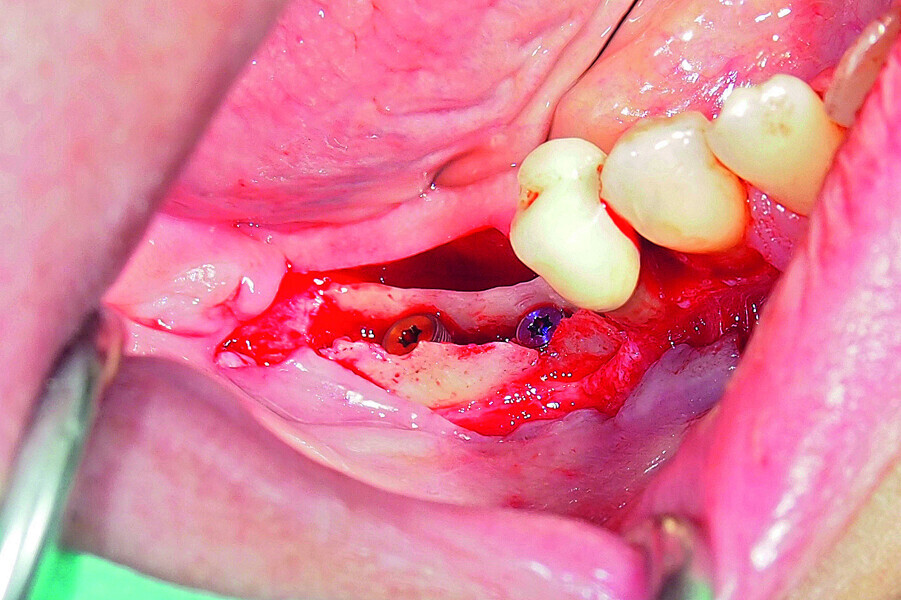

Fig. 18: Placement of two GC Aadva Standard implants with regard to the future restorative margins.

Fig. 19: Bone defect filled with xenograft and covered with an absorbable collagenous membrane.